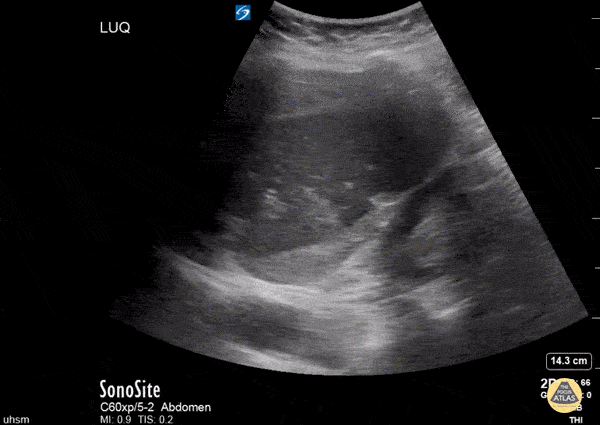

Bowel-GI - Perisplenic Hematoma

This clip is from a patient presenting with sudden onset epigastric pain with syncope. The patient had an additional episode of syncope in the ED and remained persistently hypotensive. The aorta was evaluated and was non-aneurysmal, however during FAST exam the LUQ view demonstrated a perisplenic hematoma and free fluid was also noted in Morrison’s pouch (RUQ view not shown). CT of the abdomen/pelvis later confirmed spontaneous splenic rupture. Nishant Cherian